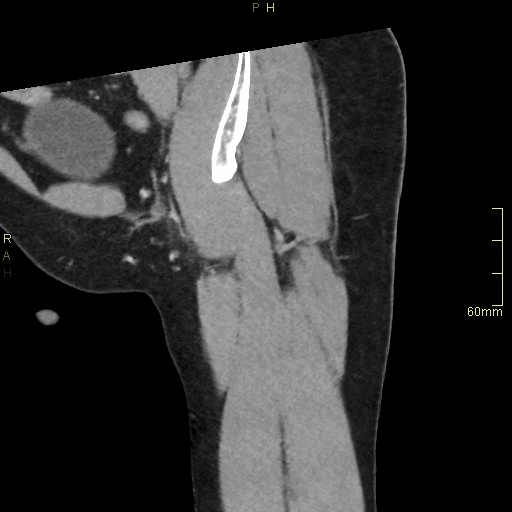

CT Hip Contrast- Soft tissue window (coronal)

CT Hip Contrast- Bone window (coronal)